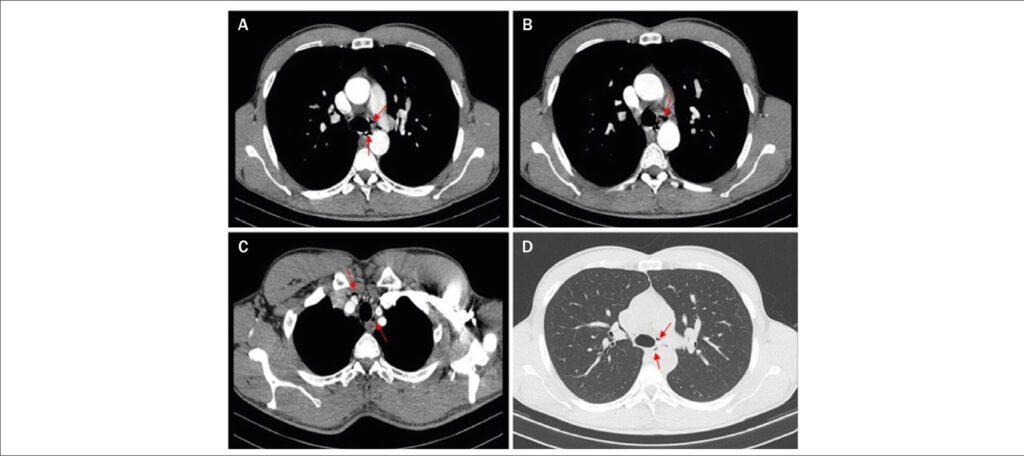

A 31-year-old male athlete presented with acute chest pain that was aggravated with swallowing after completing a marathon. Physical examination findings and his vital signs were normal. Electrocardiography revealed showed sinus rhythm, an incomplete right bundle block, and a negative T wave in V1-V2. A blood analysis showed normal D-dimer values and a slightly elevated troponin-I level (maximum at 72 hours: 0.52 ng/mL; normal, <0.07 ng/mL) with fluctuations. Chest X-ray, echocardiography, and coronary angiography findings were normal. Cardiac computed tomography (CT) revealed small gas collections on the superior and middle mediastinum compatible with spontaneous pneumomediastinum (SP). ( and ) SP is rare, usually benign, and often underdiagnosed. Intense physical exercise is a recognized cause. Cardiac CT assesses the extension, causative factors, and pathologies and discloses the diagnosis of SP when chest X-ray findings are normal.